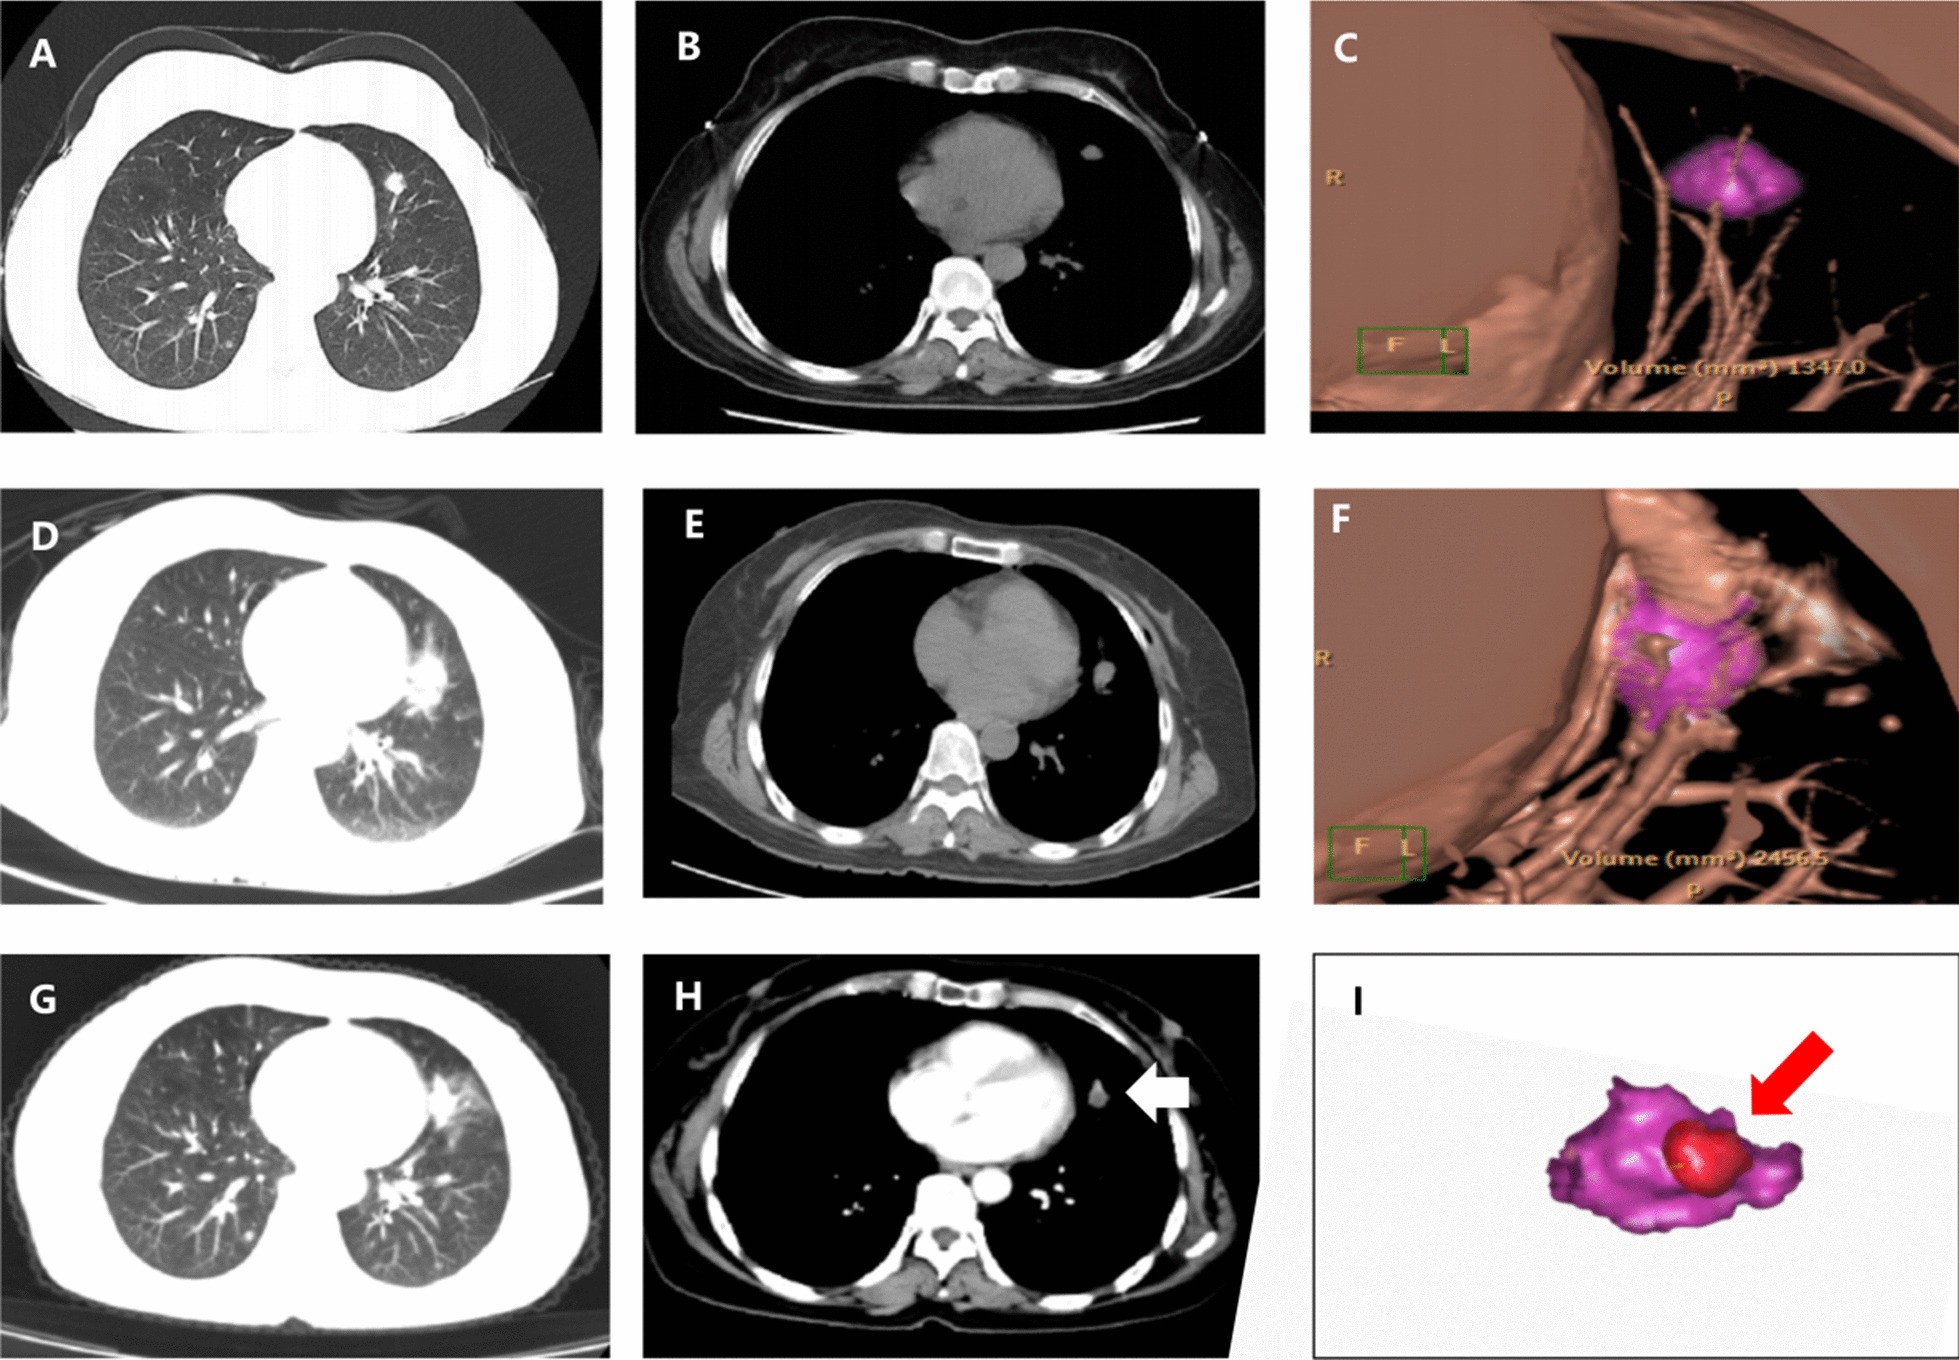

Fig. 6

a, b One lesion was clearly seen in the lung window and mediastinal window, which was pathologically confirmed as adenocarcinoma by biopsy. c 3D reconstruction revealed the size and margin of the tumor (purple color). d, e 3 days later, CT showed no pneumothorax and pleural effusion, and the ablation zone was visible. f 3D reconstruction revealed the ablation zone and spatial relationships of the tumor (purple color). g, h 4 months after MWA, there was enhancement in the ablation zone (the white arrow), which was considered as recurrence. i The images of pr-ablation (c) and postablation (f) were fused and displayed as (i). Quantitative measurement shown the minimal ablative margin was < 5 mm (the red arrow)